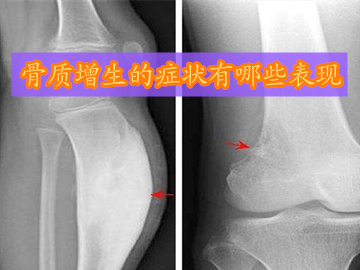

骨质增生的患病率是比较高的,大家应该对此病有所关注,若能了解骨质增生的症状,便可在得了骨质增生之后,及时发现自身的病情,及时到医院进行治疗。那么,骨质增生的症状有哪些表现?

1、膝关节骨质增生的症状:起初疼痛多发生在长时间行走或上下楼梯时,但休息或起床后会有所好转。可随着病情的发展,走平路也会感到疼痛,膝关节活动也会受到限制,同时膝关节活动时有像捻头发时所发出的响声。